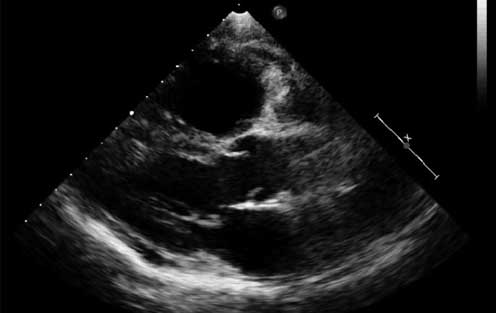

El ecocardiograma (figura 3) que se realizó en el servicio de urgencias reportó: ventrículo izquierdo no dilatado con grosor de sus paredes normales, presencia de movimiento septal paradójico con índice de excentricidad de 1.6, fracción de expulsión 60%. Cavidades derechas dilatadas, VD de 56 x 47 x 79 mm, signo de Mc Conell (+), índice de excentricidad del VD 1.9, ambas ramas de la arteria pulmonar dilatadas, con amputación de la rama izquierda. Tiempo de aceleración pulmonar de 60 ms, PSAP inferida de 60 mm Hg, la función ventricular derecha limítrofe por onda S de 11cm y TAPSE de 14 mm. Insuficiencia tricuspídea moderada vena contracta de 4 mm, sin derrame pericárdico.

Ecocardiograma transtorácico modo M bidimensional, en el que se observar dilatación del ventrículo derecho